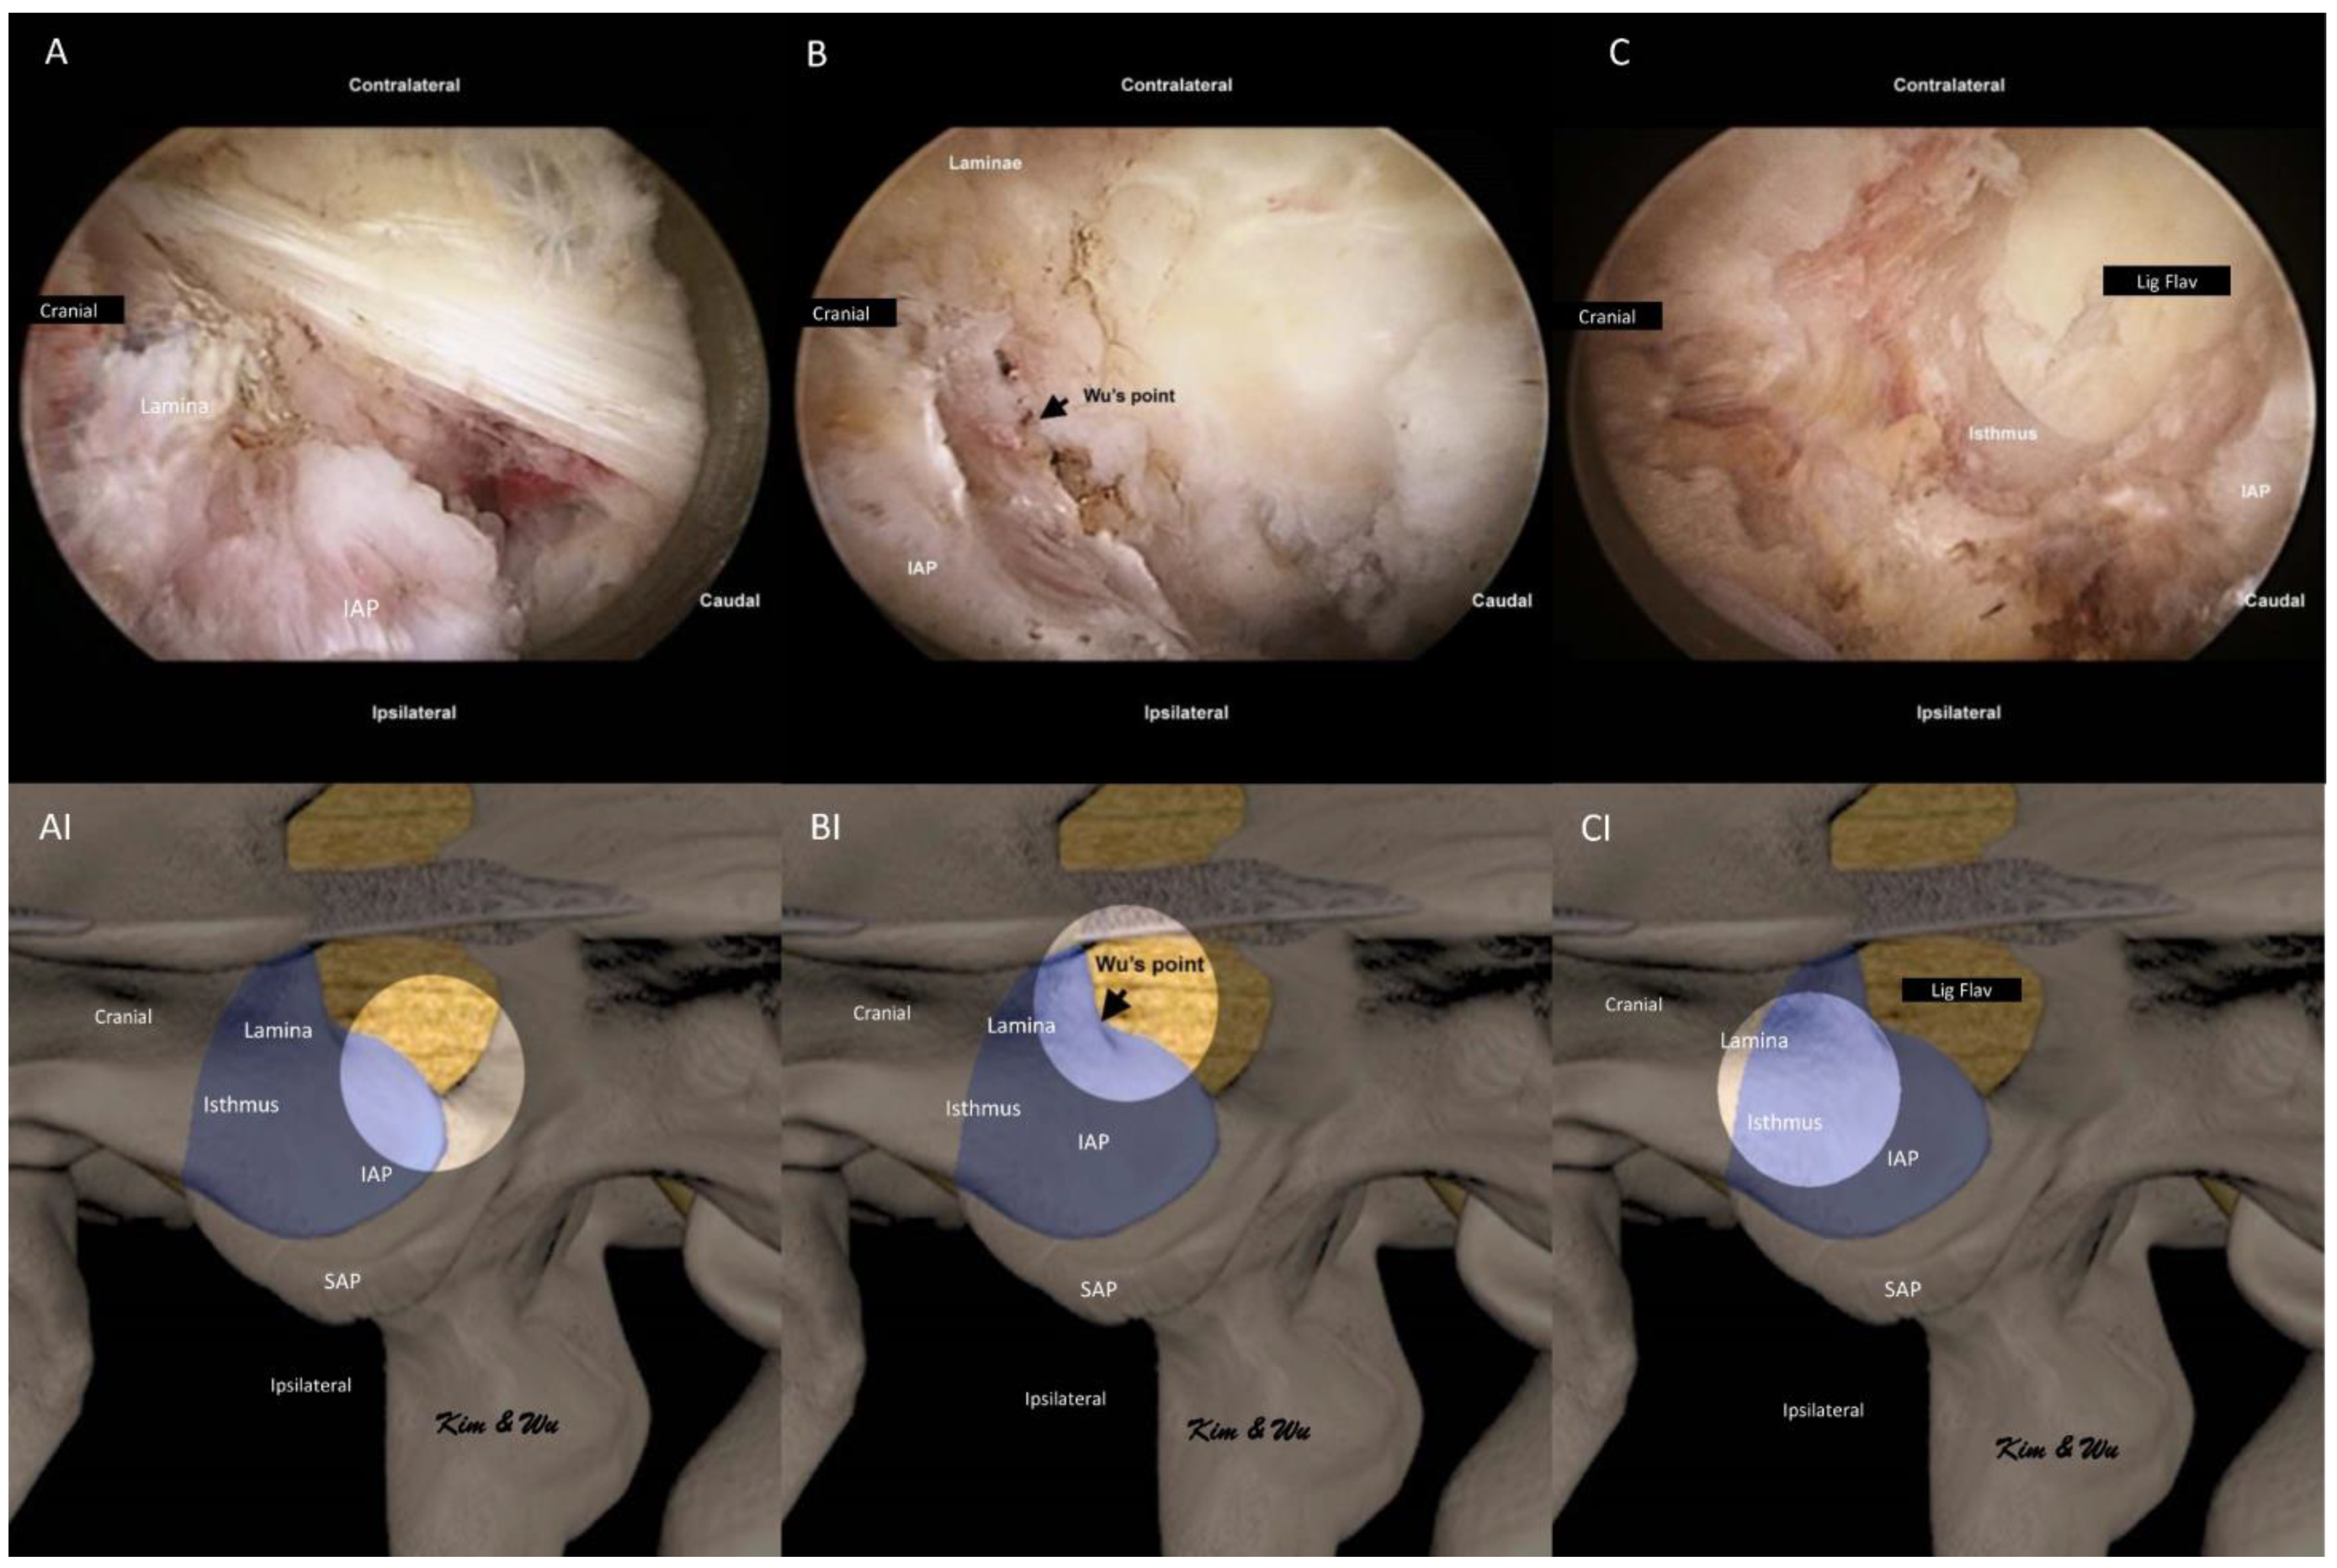

2.2. Endoscopic Surgical Anatomy of Inferior Articular Process in Endoscopic Fusion

2.4.2. Handling of Inferior Articular Process: ETLIF (I) versus ETLIF (O)

2.4.3. Superior Articular Facet Resection and Flavectomy